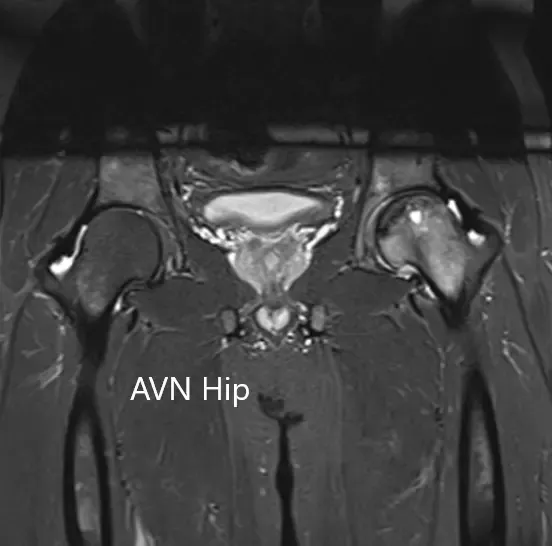

Se realizó una resonancia magnética que sugirió necrosis avascular de la cadera izquierda, estadio 3. Hubo una intensidad alterada de la señal y edema de médula ósea.

Sección coronal T2WI de la resonancia magnética que muestra AVN de cadera.